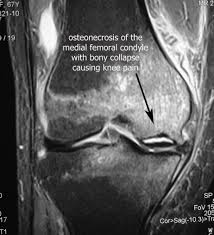

Use your time efficiently and maximize your retention of key facts and definitions with study sets created by other students studying medial femoral condyle. Given its location, these are also the easiest cartilage defects to repair. Normal irregular ossification of the femoral condyles was present in 66% of the boys and 44 % of the girls 1 in a review of knee radiographs of 147 healthy, asymptomatic children between the ages of 3 and 13 years. The flap is marked by identifying the vascular plexus on the medial condyle and incorporating a component of the network in the flap. Primary osteonecrosis of the femoral condyle shares several features with insufficiency fractures, including predominance in elderly women with factors responsible for mechanical stress (varum, obesity, trivial trauma), mechanical pain, and increased radionuclide uptake. The femoral condyle allograft has been used for resurfacing cartilage defects with mature hyaline cartilage for several decades, with very high success rates. Osteonecrosis of the medial femoral condyle presents as a sudden onset of pain on the medial side of the knee. An articular cartilage injury, or chondral injury, may occur as a result of a pivot or twist on a bent knee, similar to the motion that can cause a meniscus tear.

Medial condyle of femur from wikipedia, the free encyclopedia the medial condyle is one of the two projections on the lower extremity of femur, the other being the lateral condyle. The lateral condyle was involved in 44 % and the medial condyle in 12 %. Palpable as a hard, rounded bump to the inside of either knee joint, they are one of two condyles at the bottom of each leg bone, the other being the lateral femoral condyle. This adaptable graft option is most commonly used with oats or shell techniques to restore cartilage in the knee, but can also be used to for cartilage restoration of other joints. In a review of 79 patients with this disease, performed to establish guidelines f … The medial femoral condyle is supplied by a plexus of vessels from the descending genicular artery and the medial superior genicular artery. The medial condyle is larger than the lateral (outer) condyle due to more weight bearing caused by the centre of mass being medial to the knee. Root tear (radial tear) of the medial meniscus mild or moderate knee arthritis According to the hospital for special surgery, the medial femoral condyle is the inside of the knee, and health issues dealing with it can be treated. Osteonecrosis of the medial femoral condyle can be treated in a variety of ways depending on the stage of the disease. The medial condyle is named for its location on the inside of the knee, closer to the midline of the body, while the lateral condyle is found on the outside of the knee, away from the midline of the body. In the knee, chondromalacia is usually related to injury, overuse of the knee, and poorly aligned muscles and bones around the knee joint. Your knee mri will often show a:

Chondral injuries may accompany an injury to a ligament, such as the anterior cruciate ligament. Your knee mri will often show a: Schatzker i tibia plateau fracture. Osteonecrosis of the medial femoral condyle presents as a sudden onset of pain on the medial side of the knee. Normal irregular ossification of the femoral condyles was present in 66% of the boys and 44 % of the girls 1 in a review of knee radiographs of 147 healthy, asymptomatic children between the ages of 3 and 13 years. However, two of the patients had one or more fractures missed when they first presented. A bone fracture at this location is termed a femoral condyle fracture. According to the hospital for special surgery, the medial femoral condyle is the inside of the knee, and health issues dealing with it can be treated.

Of the six patients who had suffered an isolated fracture of their medial condyle, four of the patients had their fractures diagnosed on the first visit. The lateral condyle was involved in 44 % and the medial condyle in 12 %. It acts to support a significant amount of the patient's body weight. Cartilage can be focally damaged, producing a pot hole in the joint surface, when the knee ligaments are injured. Osteonecrosis of the medial femoral condyle presents as a sudden onset of pain on the medial side of the knee. A bone fracture at this location is termed a femoral condyle fracture. The femoral condyle is a thickened area of the femur just above the knee. One presumed mechanism of injury is a stieda fracture (avulsion injury of the medial collateral ligament at the medial femoral condyle). Root tear (radial tear) of the medial meniscus mild or moderate knee arthritis Coronal plane fracture of the lateral femoral condyle. The lesions were located on the medial femoral condyle in 8 (72.7%) cases and on the medial tibial plateau in 3 cases (27.3%). The medial femoral condyles are the bony protrusions on the inside edge of the bottom of the femur bone in each thigh. Based on the patient's antalgic gait and radiographic findings, the patient was instructed on the proper use of crutches and referred to an orthopaedic surgeon for appropriate management.

Methods sixteen knees with a small medial femoral. The lesions were located on the medial femoral condyle in 8 (72.7%) cases and on the medial tibial plateau in 3 cases (27.3%). Radiographic features it is almost always unilateral, usually affects the medial femoral condyle (but can occasionally involve the tibial plateau 9) and is often associated with a meniscal tear. In the knee, chondromalacia is usually related to injury, overuse of the knee, and poorly aligned muscles and bones around the knee joint. It acts to support a significant amount of the patient's body weight. Normal irregular ossification of the femoral condyles was present in 66% of the boys and 44 % of the girls 1 in a review of knee radiographs of 147 healthy, asymptomatic children between the ages of 3 and 13 years. The inner side of the knee or the medial femoral condyle is the most common area for a cartilage defect. A bone fracture at this location is termed a femoral condyle fracture. Palpable to either side of the knee joint when it is bent, they are known specifically as the medial and lateral femoral condyles. If there is a fracture (break) in part of the condyle, this is known as a fracture of the femoral condyle. Primary osteonecrosis of the femoral condyle shares several features with insufficiency fractures, including predominance in elderly women with factors responsible for mechanical stress (varum, obesity, trivial trauma), mechanical pain, and increased radionuclide uptake. An imbalance of the muscles around the knee (some muscles are weaker than others.) overuse (repeated bending or twisting) of the knee joint, especially during sports. Sagittal plane fracture of the medial femoral condyle.